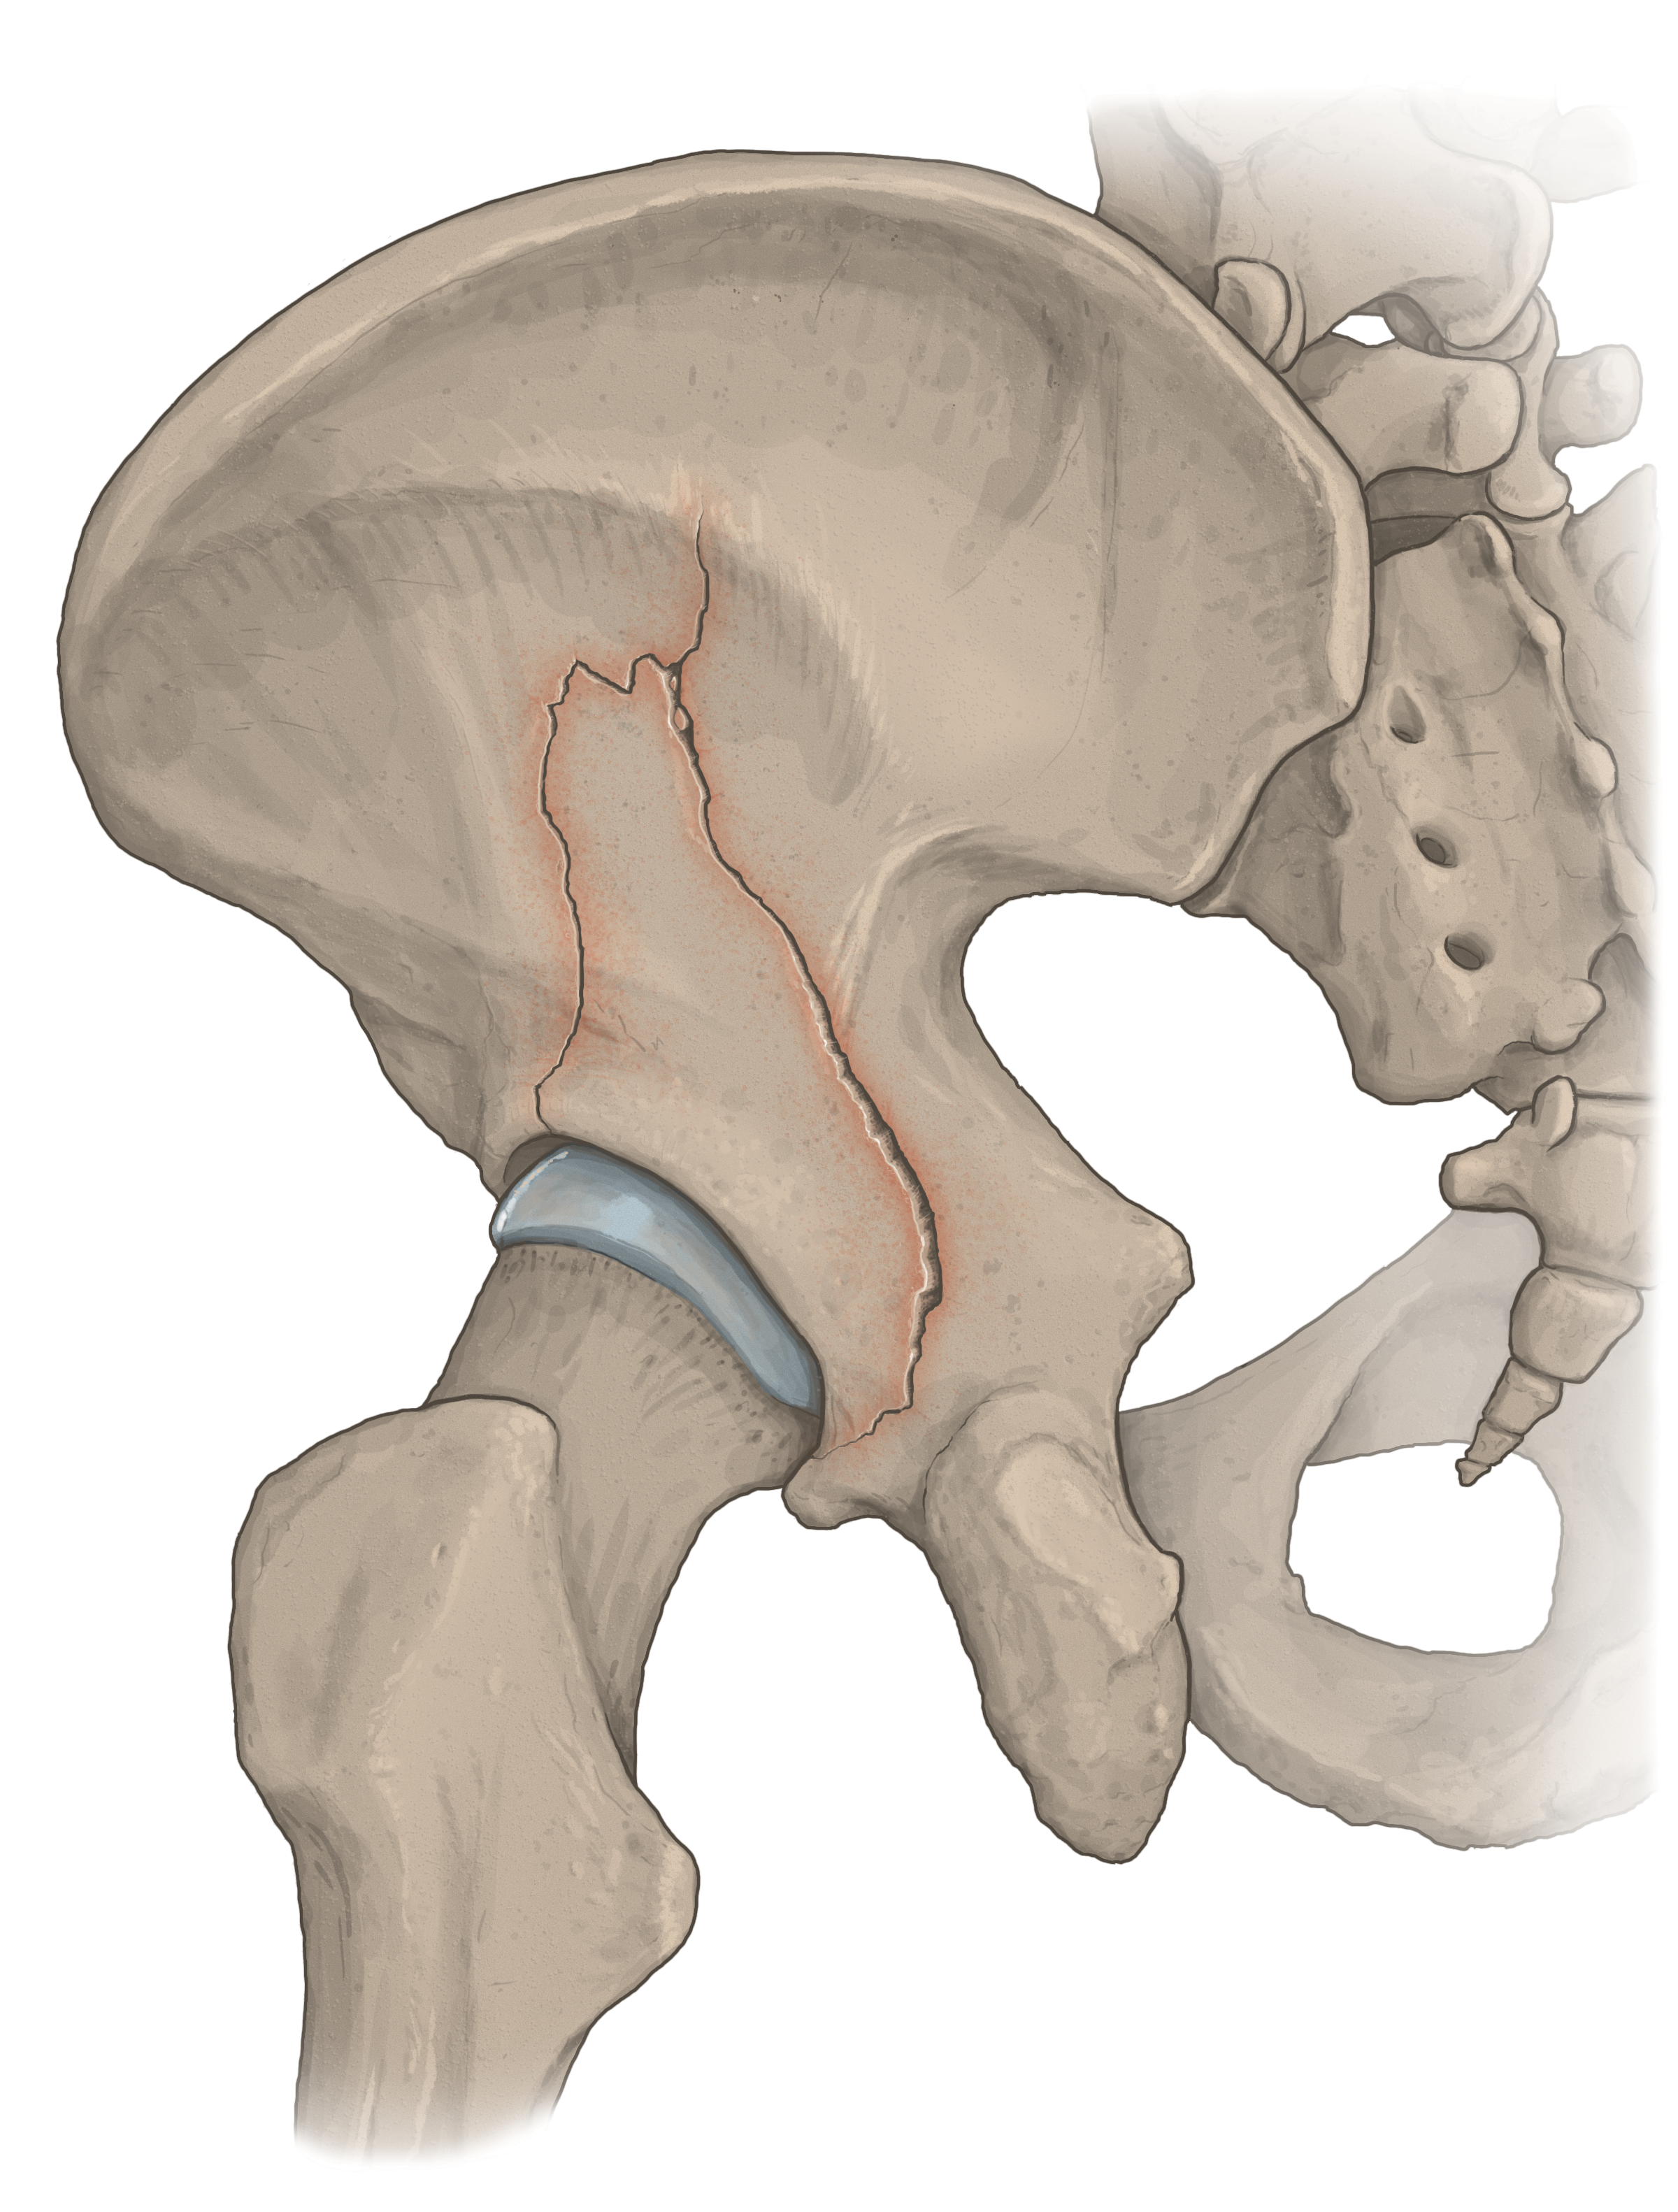

Medical-legal illustration

I can create client-specific illustrations for your personal injury or malpractice cases to both inform the jury (who often don’t have experience with hospital images) as well as gain sympathy for the affected individual. I can work directly with medical experts to ensure accuracy and admissibility in court.

Patient education

Illustrations can help patients understand surgical procedures they or a loved one are planning to have, or explain how a medication works in the body.

Licensable work

Illustrations shown below are owned by the artist and available for non-exclusive licenses, contact me for more information.